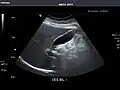

Kidneys: Right and left kidneys measure 11.5 cm and 12 cm in length respectively. No hydronephrosis. Small left lower pole kidney cyst.

Left kidney -